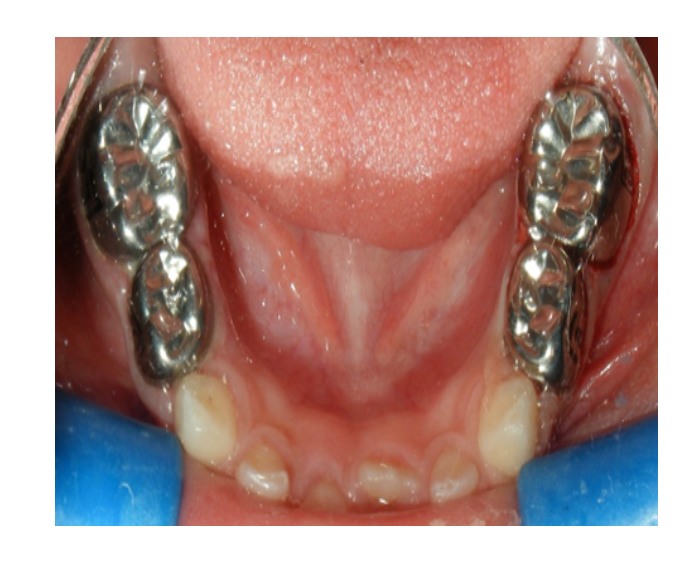

Mordida cruzada posterior bilateral